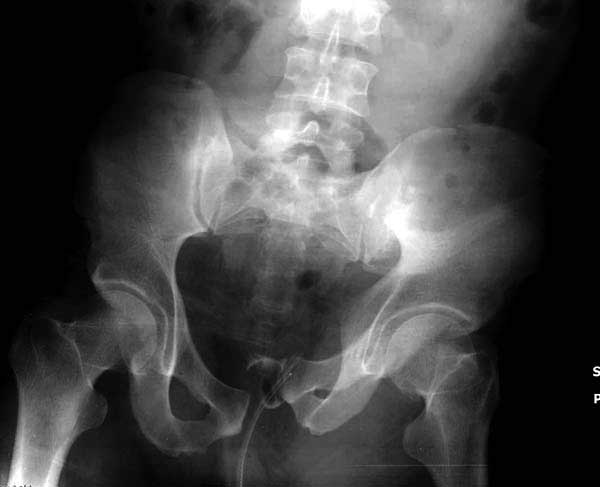

Подробное изучение инлет и оутлет, а также КТ срезов, поможет разобраться в диагностике. Без обследования случай усложнится. Операция непростая, кроме технических навыков, надо иметь стандартные инструменты для операции.

Здесь представлен случай 38 летнего больного (падение с высоты 9 метров) с нарушением тазового кольца. При поступлении для стабилизации передне-нижний аппарат наружной фиксации и на 6й день, вчера, операция из двух доступов.

Представлены снимки техники проведения стержней. Через место прикрепления прямой мышцы в Inferior Iliac Spine в направления вырезки создается жесткость. Weber clamp изнутри таза для репозиции, и фиксация после репозиции перелома крыла подвздошной кости. Наружный аппарат удален, нагрузка предполагается через два месяца.